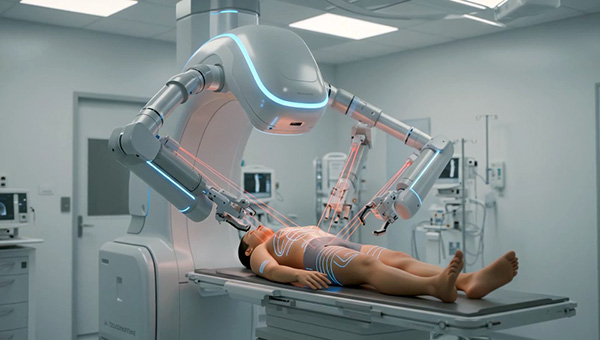

Will I be treated by robots or human doctors?

How does AI improve the safety of surgeries?